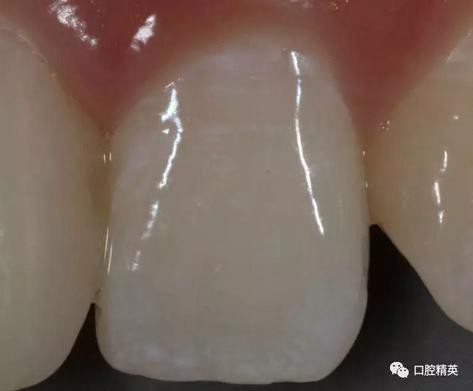

比色,記錄鄰牙顏色細節(jié)

修復體展示

口內(nèi)正側(cè)位及切端特寫